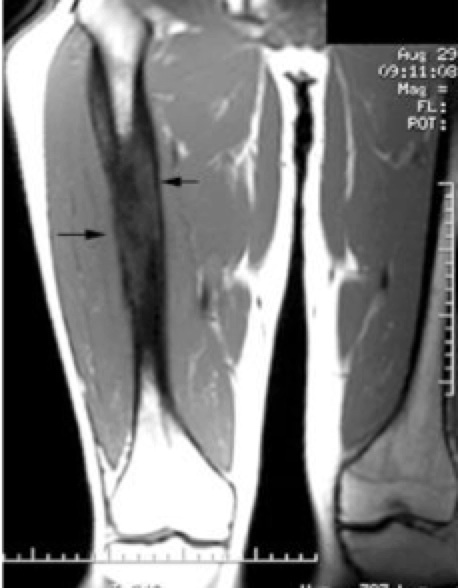

Workup consists of biopsy, cytogenetics, CT and MR imaging, including chest CT. Bone scan, ±PET scan, bone marrow biopsy, LDH and routine chemistries. Disease can spread to the lung, therefore imaging of the chest is required.

• CT and MRI of primary disease

Current volume recommendations for volume mandate fused MRI/CT to identify the full tumor extent. The entire bony abnormalilty and soft tissue mass are included as identified at diagnosis, before any treatment. This is the GTV. The CTV is the initial (pre-treatment extent of disease) GTV + 2 cm margin to cover potential occult tumor. The PTV is added per institutional setup uncertainty, generally 5 mm to 1 cm.